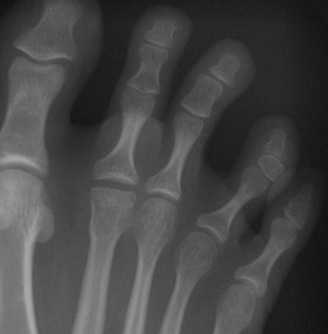

- Болезнь КеллераII. На снимках выявляются патологические изменения в головке пораженной плюсневой кости. В зависимости от срока заболевания может обнаруживаться остеопороз, уплотнение и деформация головки плюсневой кости, ее патологический перелом и дефрагментация.

Формализованный протокол. СТОПА (схема). Болезнь Келера 2.

Определяется деформация и уплощение головки 2, 3, 4 плюсневой кости. На фоне разряжения структуры костной ткани головки дифференцируются плотные островки с четкими, неровными контурами. Дистальный метафиз 2 плюсневой кости несколько утолщен, по всей видимости, за счет периостальных наслоений. Суставная щель во 2 плюсне - фаланговом суставе расширена.

Суставные поверхности, образующие плюсне-фаланговый сустав, инконгруэнтны, форма суставных поверхностей деформирована, уплощена, склерозирована в области . Величина суставных поверхностей увеличена за счет краевых костных разрастаний. Контуры замыкательных пластинок эпифизов ровные, чёткие. Подхрящевой (субхондральный) остеосклероз, как свидетельство функциональной несостоятельности суставных хрящей и свидетельствующий о перегрузке костной ткани, определяется в области . По краям суставных поверхностей определяются костные разрастания (свидетельствуют о функциональной несостоятельности суставных хрящей).

ДИАГНОСТИЧЕСКОЕ ЗАКЛЮЧЕНИЕ:

Остеохондропатия головки 2 плюсневой кости - болезнь Келера 2 правой стопы, картина деформирующего артроза 2 плюсне-фалангового сустава 2 (второй) стадии по классификации Н.С. Косинской.